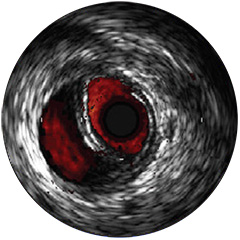

Digitale IVUS- Bildverarbeitung

-Bildverarbeitung

Bildverarbeitung

IntraSight ist auf Basis einer intelligenten, anwendungsbasierten Plattform konzipiert, die sich bei neuen verfügbaren Anwendungen und Modalitäten an die sich ändernden Anforderungen Ihres Labors anpassen lässt – und das ohne neue Hardware erwerben zu müssen. Nur IntraSight von Philips bietet Ihnen erstklassige Bildverarbeitungs- und Physiologie-Tools mit iFR, iFR-Koregistrierung*, FFR, IVUS, IVUS-Koregistrierung* und Angio+*. Dank seiner modularen Architektur bleibt IntraSight über die neuesten Entwicklungen und wichtigen Sicherheitsupdates auf dem Laufenden.